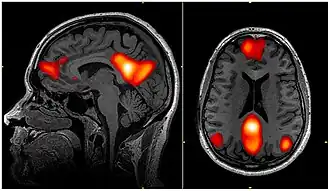

Dynamic functional connectivity (DFC) refers to the observed phenomenon that functional connectivity changes over a short time. Dynamic functional connectivity is a recent expansion on traditional functional connectivity analysis which typically assumes that functional networks are static in time. DFC is related to a variety of different neurological disorders, and has been suggested to be a more accurate representation of functional brain networks. The primary tool for analyzing DFC is fMRI, but DFC has also been observed with several other mediums. DFC is a recent development within the field of functional neuroimaging whose discovery was motivated by the observation of temporal variability in the rising field of steady state connectivity research.

Functional connectivity refers to the functionally integrated relationship between spatially separated brain regions. Unlike structural connectivity which looks for physical connections in the brain, functional connectivity is related to similar patterns of activation in different brain regions regardless of the apparent physical connectedness of the regions.[1] This type of connectivity was discovered in the mid-1990s and has been seen primarily using fMRI and Positron emission tomography.[2] Functional connectivity is usually measured during resting state fMRI and is typically analyzed in terms of correlation, coherence, and spatial grouping based on temporal similarities.[3] These methods have been used to show that functional connectivity is related to behavior in a variety of different tasks, and that it has a neural basis. These methods assume the functional connections in the brain remain constant in a short time over a task or period of data collection.

Because DFC is such a new field, much of the research related to it is conducted to validate the relevance of these dynamic changes rather than explore their implications; however, many critical findings have been made that help the scientific community better understand the brain. Analysis of dynamic functional connectivity has shown that far from being completely static, the functional networks of the brain fluctuate on the scale of seconds to minutes. These changes are generally seen as movements from one short term state to another, rather than continuous shifts.[3] Many studies have shown reproducible patterns of network activity that move throughout the brain. These patterns have been seen in both animals and humans, and are present at only certain points during a scanner session.[7] In addition to showing transient brain states, DFC analysis has shown a distinct hierarchical organization of the networks of the brain. Connectivity between bilaterally symmetric regions is the most stable form of connectivity in the brain, followed by other regions with direct anatomical connections. Steady state functional connectivity networks exist and have physiological relevance, but have less temporal stability than the anatomical networks. Finally, some functional networks are fleeting enough to only be seen with DFC analysis. These networks also possess physiological relevance but are much less temporally stable than the other networks in the brain.[8]